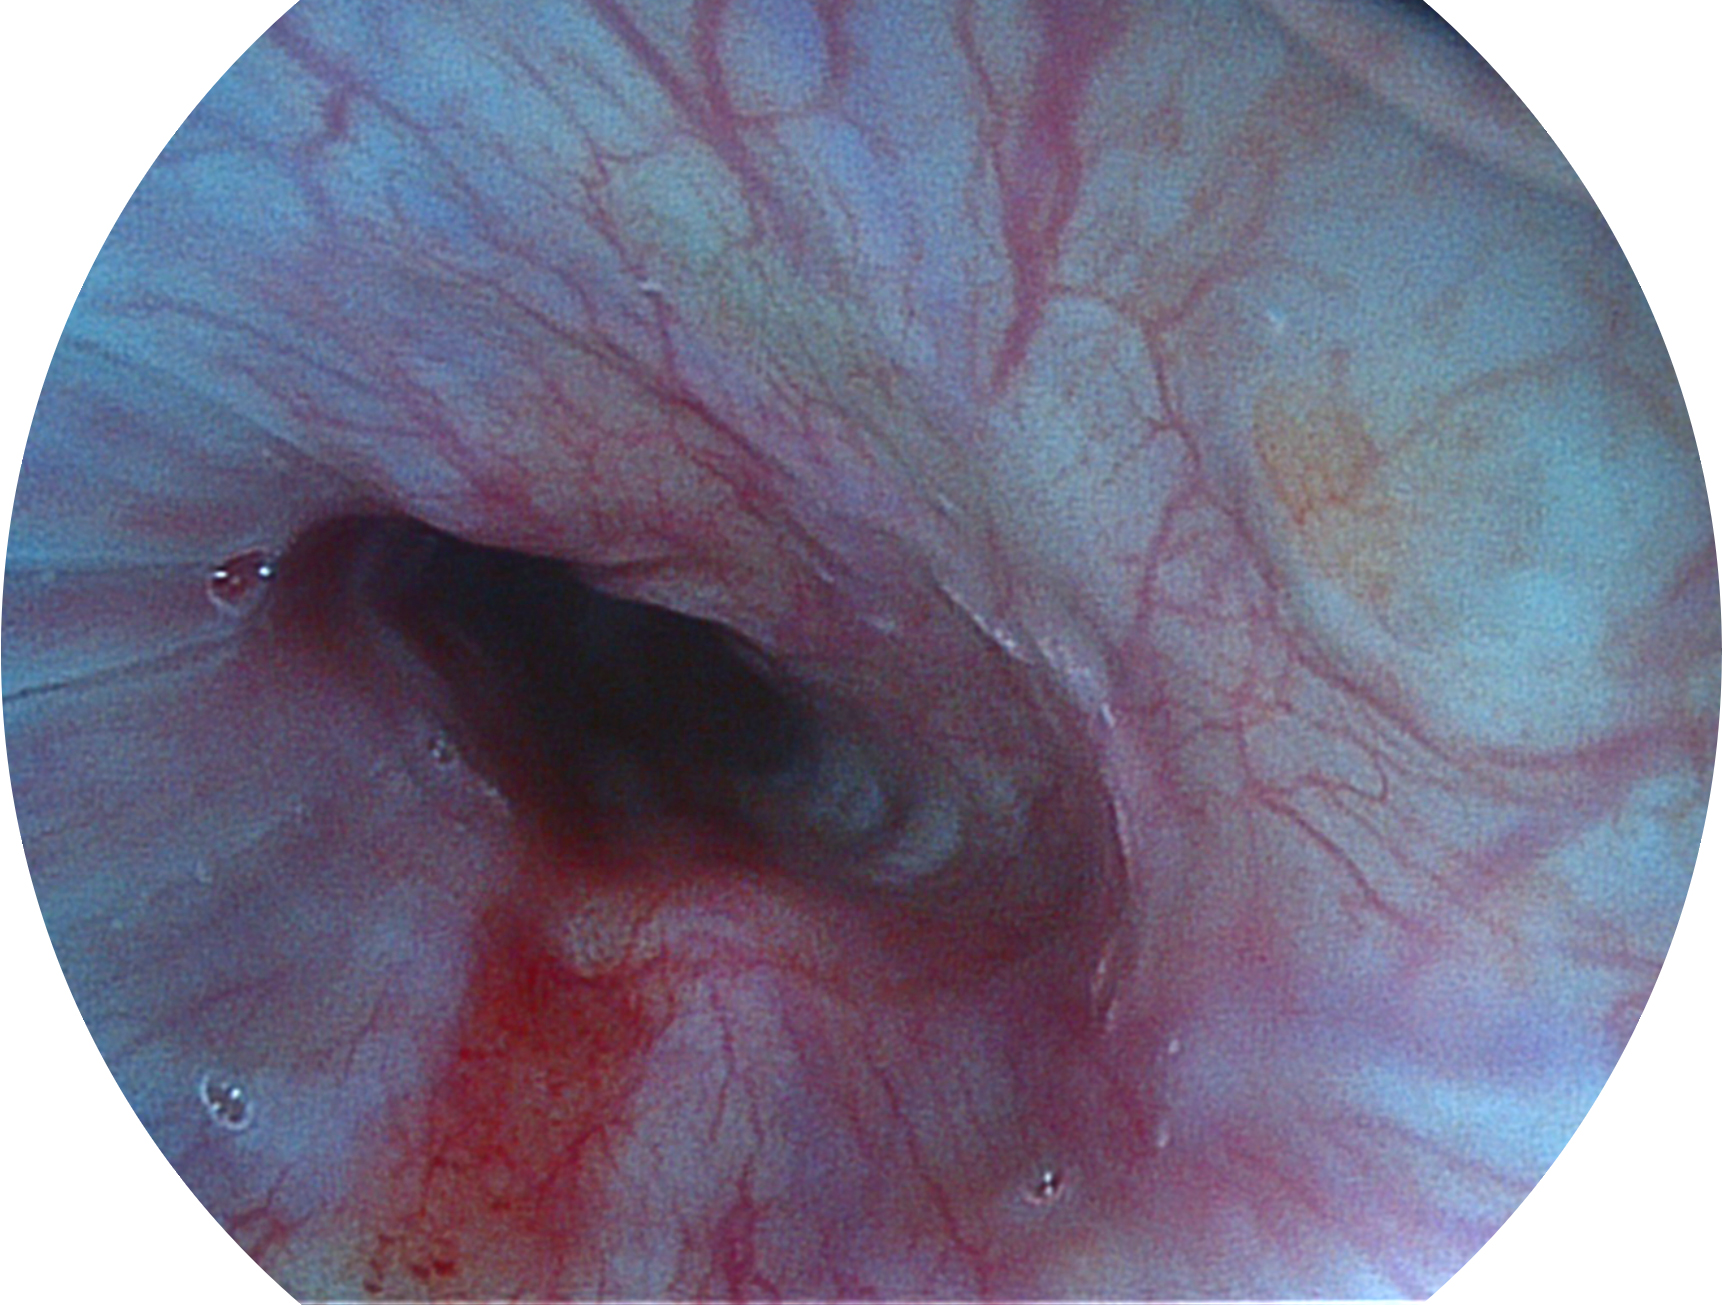

新葡的京集团8814检测站新开发的内镜染色技术,主要是基于多波长LED 光源的开发,VLS-55Q 四波长LED 光源是由四个不同颜色的LED光按照相应照明模式所规定的特定发光比例进行合束后形成,合束后形成的照明光的光谱由红光、绿光、蓝光及蓝紫光这四个不同的波段范围构成。具有更高光谱自由度,通过光谱比例的控制,实现了聚谱成像技术,英文全称为“Spectral Focused Imaging, SFI”,缩写为“SFI”和光电复合染色成像技术,英文全称为“Versatile Intelligent Staining Technology, VIST”,缩写为“VIST”。